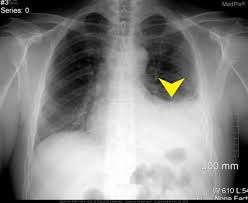

The main treatment for hemopneumothorax is called chest tube thoracostomy. This procedure involves placing a hollow plastic tube between the ribs into the area around the lungs in order to drain the air and blood. The tube may be connected to a machine to help with the drainage.